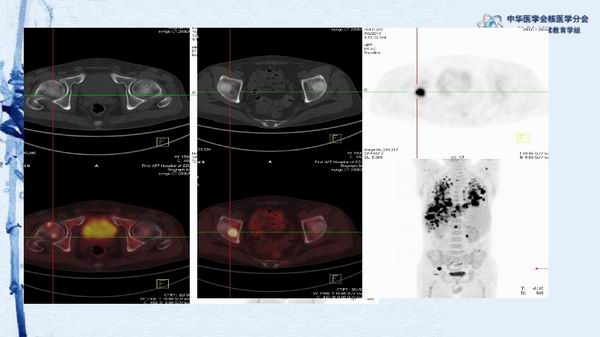

病例49:PET-CT显像诊断淋巴瘤相关噬血细胞综合征一例-【CSNM继教学组】程兵 郑州大学第一附属医院